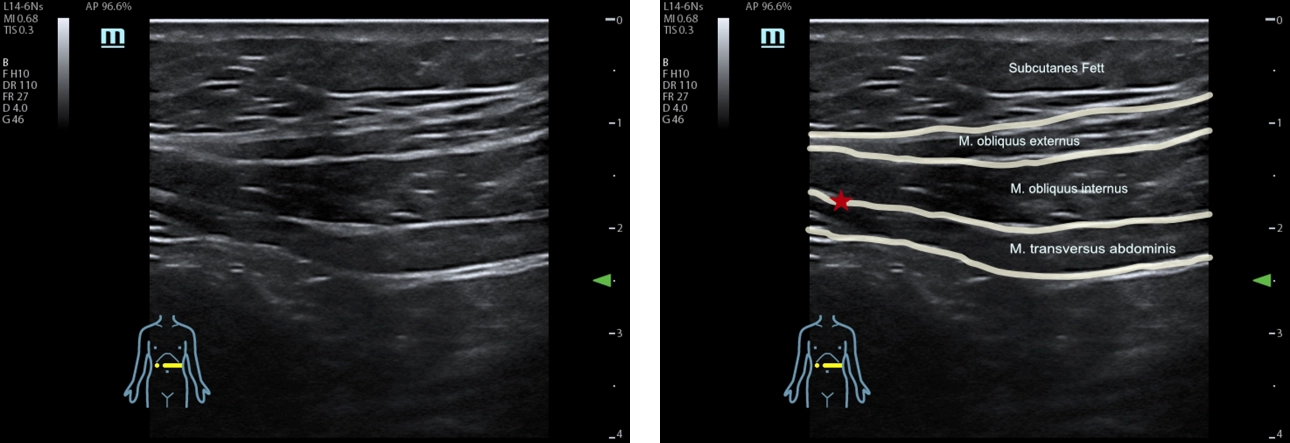

Sonoanatomie laterale Rumpfwandschichten, subcostal links. Roter Stern: Zielstruktur der (subcostalen) Transversus abdominal plane Blockade

Das an den Standorten Calw und Nagold verwendete Ultraschallgerät TE7 von Mindray biete aufgrund seiner hohen Abbildungsleistung beste Voraussetzungen, um solche Blockaden in die vordere Bauchwand zu setzen, erläutert Döffert: „Mit dem MSK Preset können wir die Muskulatur sehr gut abgrenzen. Dadurch gewinnen wir nicht nur an Präzision und Sicherheit, wenn wir die Injektion setzen, sondern auch der Zeitaufwand hält sich in Grenzen.“

Eine Rumpfblockade dagegen führen Döffert und seine Kollegen dann durch, wenn der Patient bereits in Vollnarkose liegt. Üblicherweise erfolgt die Installation der Lokalanästhetika über mehrere Einstichstellen in unterschiedlichen Quadranten. Die Flüssigkeit wird zwischen zwei Muskelschichten injiziert, um diese voneinander zu trennen. „Im Ultraschall kann ich genau verfolgen, wann ich in der richtigen Schicht bin, wie die Muskelschichten auseinander gehen und sich das Lokalanästhetikum spindelförmig ausbreitet. Selbst bei sehr kräftigen Patienten mit einem Body Mass Index 50 plus erreichen wir mit unserem Gerät noch eine ausreichende Auflösung, um die Zielstrukturen sicher darzustellen.“ In besonderem Maße profitieren auch antikoagulierte Patienten von der neuartigen Blockadetechnik, denn da sie weniger invasiv ist, besteht auch kein erhöhtes Blutungsrisiko.